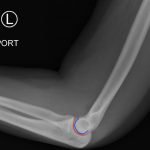

Elbow dislocations are classified by the position of the radio-ulnar joint relative to the humerus.1 Images 1, 2, and 3 show a left posterior elbow dislocation; the radius and ulna are displaced posteriorly with respect to the distal humerus. The lateral view of the elbow most clearly shows this: trochlear notch of the ulna is empty and displaced posteriorly relative to the trochlea. There is no associated fracture. Images 4 and 5 show the elbow status-post reduction, demonstrating proper alignment of the distal humerus with the radius and ulna.